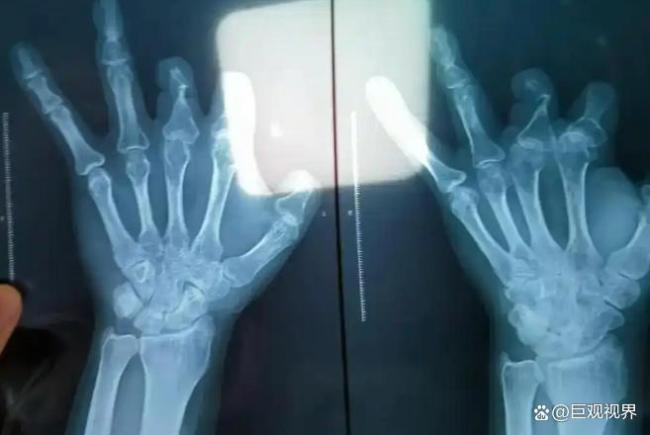

三年后,王海森得知当年手术用的昂贵器材根本没植入体内。他在老家医院拍了X光片,发现手指伤口处空荡荡的,那个花了他3万多的器材真的消失了。这个吻合装置上带着不锈钢针,不可能被人体吸收,唯一的可能就是手术时根本没使用。

后来王福建的助手爆料,那些没被使用的器材要么被丢进垃圾桶,要么被偷偷缝在患者血管旁边的肉里。因为被投诉过几次后,王福建想出了这个损招,只要器材在体内,哪怕没用到血管上,拍X光能看到就能蒙混过关。